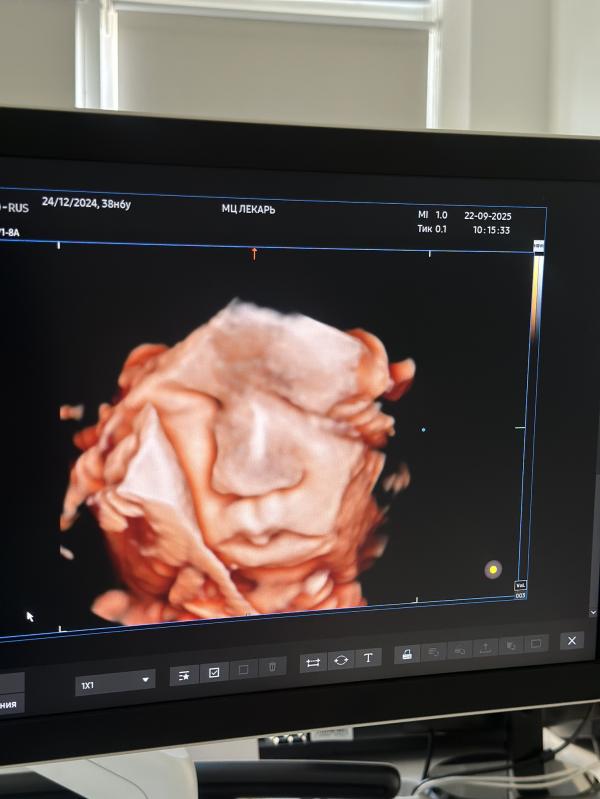

post image 2

Предродовое УЗИ проводится в 38 недель